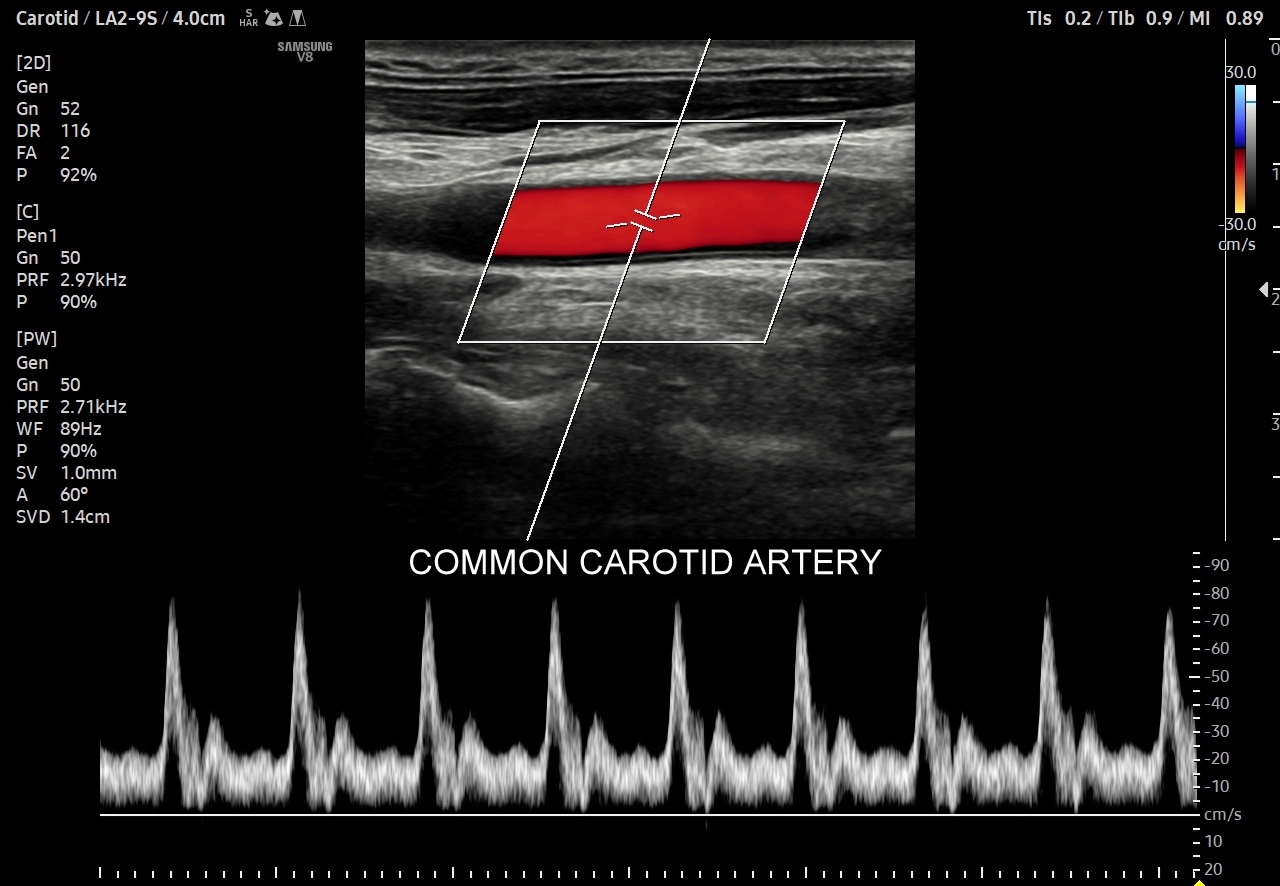

Profil przepływu tętniczego cechuje się pulsacyjnością. W składu pulsu wchodzi składowa skurczowa i rozkurczowa. Składowa skurczowa rejestrowana jest we wszystkich drożnych tętnicach i jest zależna głównie od prawidłowo funkcjonującego serca. Składowe rozkurczowe, a konkretnie kształty spektrum prędkości przepływu krwi w naczyniach w trakcie rozkurczu komór serca, różnią się w zależności od łożyska naczyniowego. Otóż składowa rozkurczowa zależy przede wszystkim od unaczynionej przez tętnicę tkanki bądź narządu, a także od kurczących się elastycznych tętnic. Pomiędzy składową skurczową a rozkurczową często obserwuje się złamki odpowiadające chwilowemu wstecznemu przepływowi krwi związanemu z zamykaniem się zastawek aortalnej bądź płucnej, jak i odbiciem się fali tętniczej od naczyń na poziomie mikrokrążenia (ang. water-hammer effect). Biorąc pod uwagę kształt fali spektrum przepływu możemy je podzielić na te o 1/ niskiej pulsacyjności, 2/ umiarkowanej pulsacyjności, 3/ wysokiej pulsacyjności.

- Profile o niskiej pulsacyjności (ang. low-pulsatility) cechują się szerokim pikiem skurczowym, praktycznie ciągłym przepływem przez całą fazę rozkurczową i monofazowością. Profile tego typu występują w tętnicach unaczyniających bezpośrednio mózg, siatkówkę, tarczycę, wątrobę, śledzionę, nerki.

Oprócz przepływów typowo niskooporowych oraz typowo wysokooporowych istnieją profile przepływów o pośredniej charakterystyce, np. w tętnicy szyjnej wspólnej. Z kolei w przypadku tętnic kręgowych w zależności od ich szerokości fizjologicznym jest obserwowanie zarówno profilu niskooporowego w przypadku dużej średnicy, jak i wysokooporowego w przypadku małej średnicy.